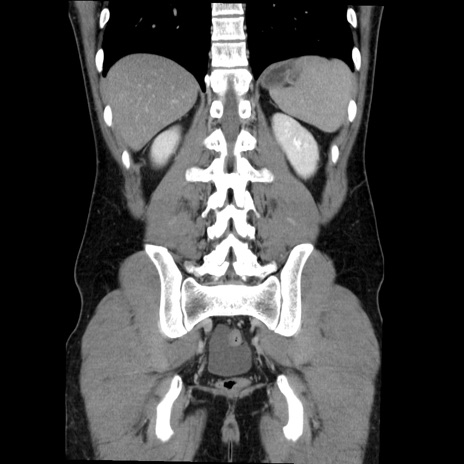

症例36(冠状断像)

【症例】20歳代 男性

【主訴】心窩部痛

【現病歴】今朝より上腹部痛あり。一旦軽快していたが再度出現したため救急要請。昨日夕に白身の魚を含む刺身を食べた。

【身体所見】BP 136/89mmHg、HR 74/min、BT 37.0℃、腹部:膨満、軟、心窩部に圧痛あり。反跳痛なし、筋性防御なし、腸雑音やや亢進あり。

【データ】WBC 17700、CRP 0.48